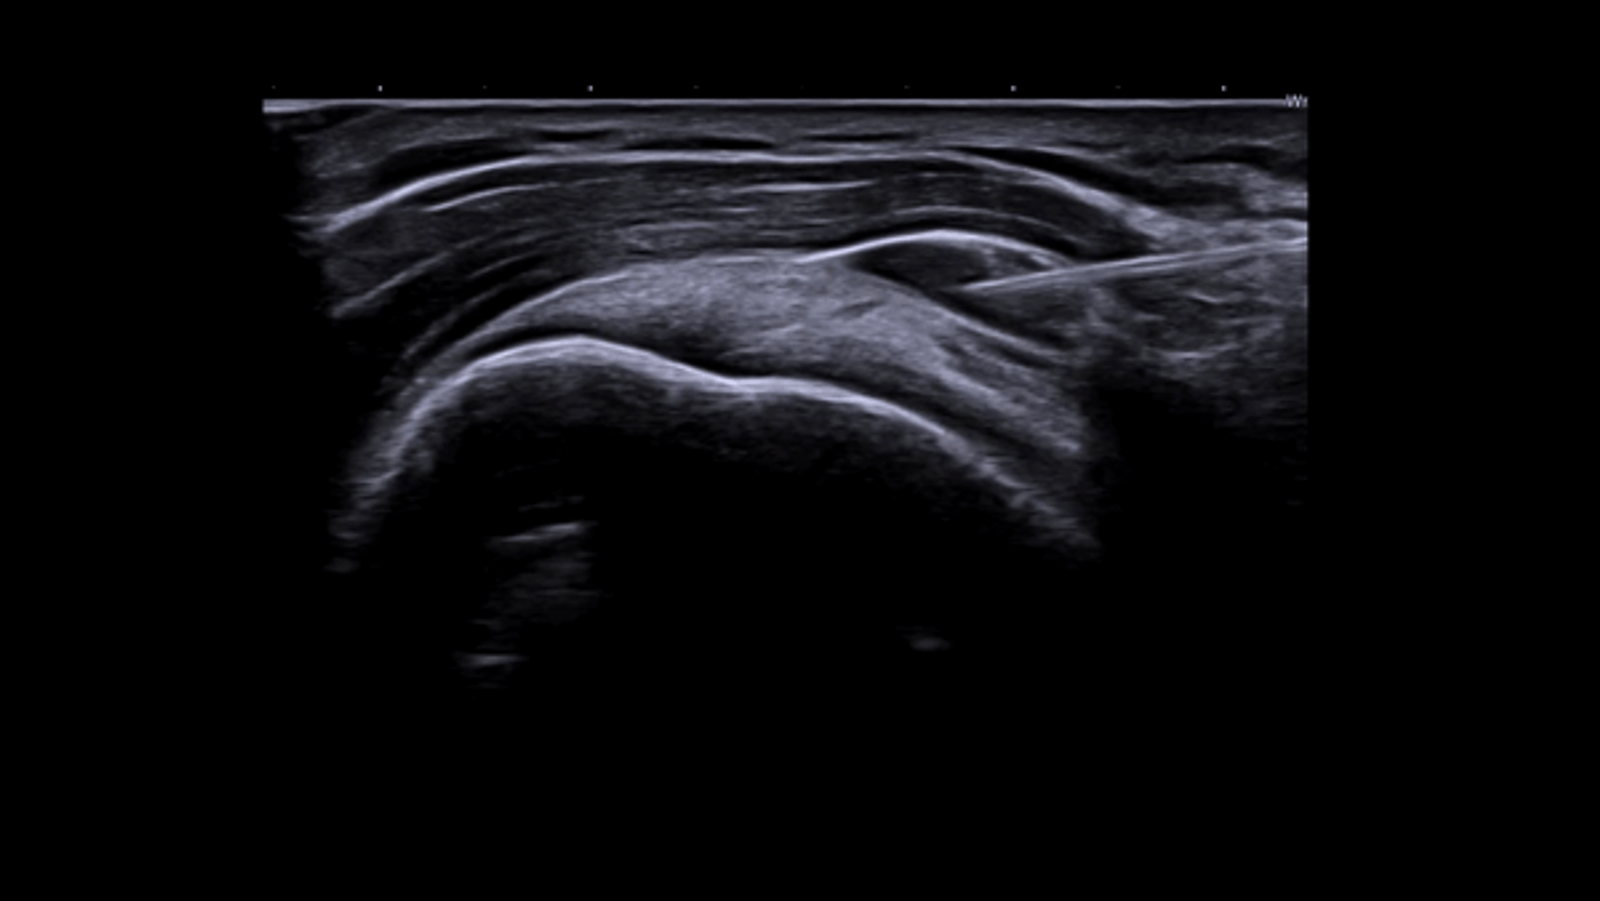

InterventionalAI Needle Recognition uses pattern recognition algorithms to identify and enhance the needle in real time during ultrasound-guided procedures. The system detects the needle shaft and tip against the surrounding tissue, applying visual enhancement that makes the needle clearly visible even at steep insertion angles or in deep tissue where conventional B-mode imaging struggles to distinguish the needle from background anatomy. Combined with GE's B-Steer+ beam steering technology, which optimizes the ultrasound beam angle relative to the needle, AI Needle Recognition gives interventional operators confident needle tracking during biopsies, nerve blocks, vascular access, and joint injections.

AI Needle Recognition applies image processing algorithms trained to identify the linear reflective pattern of a needle within ultrasound images. Unlike conventional needle enhancement that relies solely on compound imaging angles, the AI approach detects the needle structure through pattern recognition, maintaining visualization even when the needle enters at steep angles that would normally produce weak reflections. B-Steer+ complements this by electronically steering the ultrasound beam to optimize the insonation angle relative to the needle trajectory, maximizing specular reflection from the needle surface. The combined system displays the needle and surrounding anatomy simultaneously without the image quality tradeoffs that older beam-steering methods introduced. Multi-plane visualization options show the needle in both longitudinal and transverse orientations, giving operators spatial awareness of the needle position relative to target structures and critical anatomy to avoid. The system works with a range of needle gauges and types, from fine-needle aspiration needles to larger biopsy needles. For emergency medicine, anesthesiology, interventional radiology, and pain management, AI Needle Recognition reduces the number of needle passes required to reach the target, decreasing procedure time and complication risk.